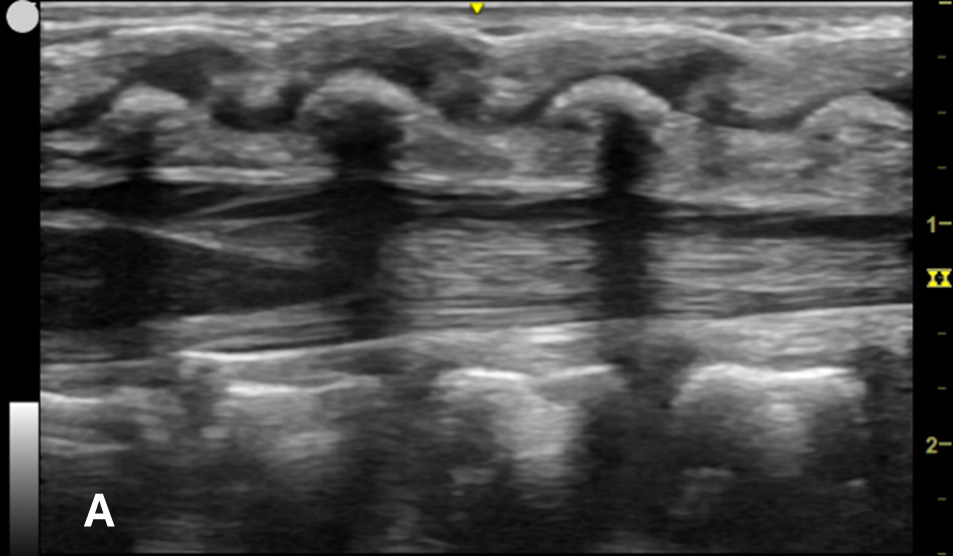

US-assisted LP is performed using the high-frequency linear transducer at the infant’s lower lumbar spine, with the patient either in a lateral recumbent position or an upright sitting position. The standard LP position, in which the neck and hips are flexed, should be used to locate the optimal site for needle insertion. Warm gel should be used during US to provide comfort and reduce the risk of hypothermia in infants. Align the transducer along the spinous process of the lumbar spine above the level of intercristal line to obtain a sagittal view of the spinal canal. The tapered CM is identified, below which any space is safe for needle insertion. The amount of anechoic cerebrospinal fluid (CSF) can be grossly compared in each space to locate the ideal LP site to obtain maximal CSF volume. (Figure 1A-B) The next step is to mark the skin at this optimal intervertebral level using a marking pen. Additionally, we recommend measuring the depth from the skin to the posterior border of the subarachnoid space using calipers, ensuring an angle of entry of 30–45 degrees. (Figure 1C) This allows the proceduralist to more precisely estimate the minimum needle depth needed to reach the subarachnoid space.

Figure 1A - Corresponding US image showing the target area of the lower spinal canal in sagittal/longitudinal view.

Figure 1B - Structures in the target area: SP (spinous process), CSF (cerebrospinal fluid), CM (conus medullaris), and CE (cauda equina).